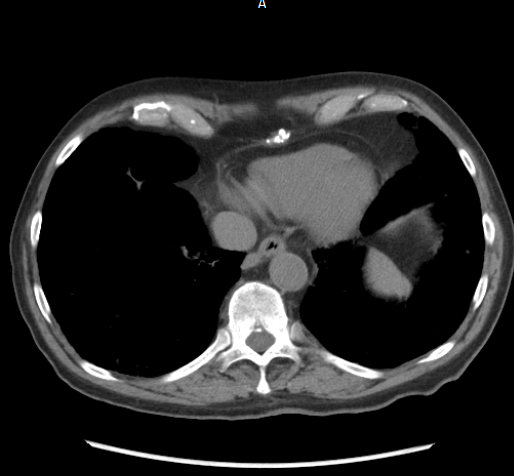

We provide high-fidelity training data for Medical Diagnostics and Intelligent Business Systems. Our assets include the premier UAE-RAD 135K Radiology dataset, comprehensive Pathology reports, Strategic Financial datasets, and 15+ years of Productivity analytics. Sourced ethically and delivered with precision to fuel your next-gen AI models.

High-quality studies covering Trauma, Oncology, and Cardiac diagnostics.

We provide radiologist-linked diagnostic narratives, pathology reports, DICOM images, and expert-verified Financial data and Timesheets, ensuring a solid ground truth for model validation.